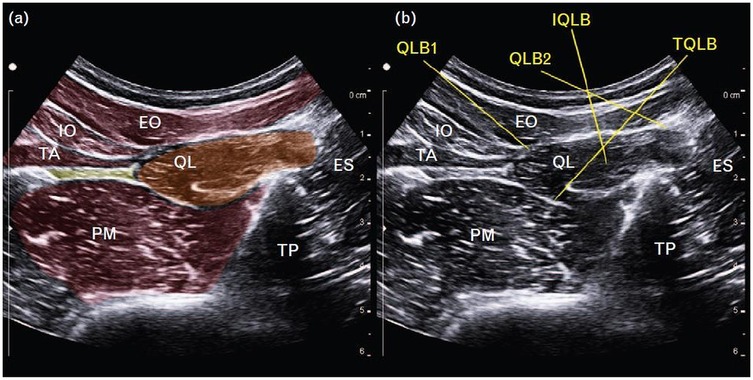

4.3 Anterior quadratus lumborum block

The anterior QLB (QLB3), first described by Børglum and colleagues (42), is a transmuscular technique in which local anesthetic is deposited into the fascial plane between the anterior surface of the QL and the PM muscle (Figure 5). This anatomical space permits cranial spread of anesthetic through the diaphragmatic arcuate ligaments and the endothoracic fascia, thereby reaching the thoracic paravertebral space (39, 43). As a result, QLB3 can achieve both somatic and sympathetic blockade, depending on the extent of cranio-caudal diffusion (37, 44).

Figure 5

Ultrasound images of the lumbar region display anatomical structures and needle trajectory. Labeled structures include the quadratus lumborum (QL), psoas major (PM), transverse abdominis (TA), oblique external (OE), oblique internal (OI), aorta, and L4 vertebrae. The erector spinae muscle is also visible. The left image highlights a QLB 3 injection path, while the right image presents a clear view of the lumbar anatomy. The images are dated 4th September 2018.

Figure 5. Anterior quadratus lumborum block (QLB). TA, transversus abdominis; IO, internal oblique; EO, external oblique; PM, psoas major [Reproduced from Vamnes et al. (58). © 2021 by the Croatian Medical Journal. Distributed under the Creative Commons Attribution License, CC BY 4.0].

In the conventional transmuscular approach, the patient is positioned laterally. A low-frequency convex probe is placed vertically above the iliac crest. The needle is inserted in-plane from the posterior margin of the probe and advanced anteromedially through the QL muscle (Figure 6a). Ultrasound visualization of the posterior vertebral and paravertebral structures is essential. Once the tip reaches the interfascial plane between the QL and PM, local anesthetic is injected, displacing the PM anteriorly (Figure 6b).